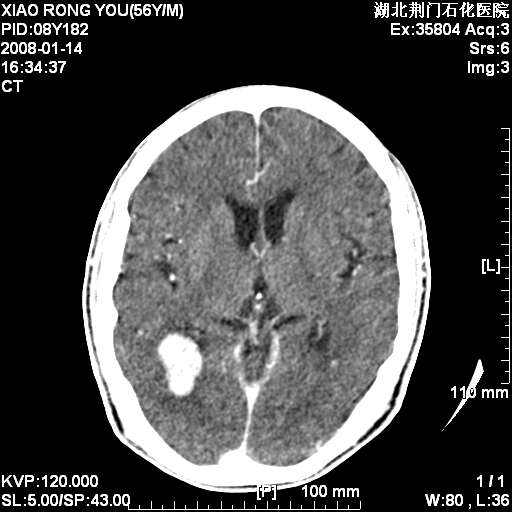

3天后增强

多发,考虑转移

转移瘤,前后对比可发现复查片左顶叶出现一低密度灶

病变范围在一个多月时间增大,且密度不均周围有税种,并且多发!考虑转移瘤!

左枕/顶叶出现新病灶,转移瘤